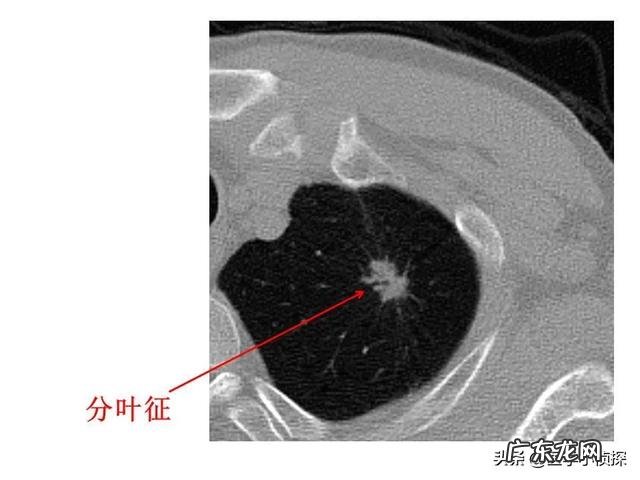

还有亚实性结节 , 而且亚实性结节又分为下面这种纯磨玻璃结节

文章插图

以及上面这种混杂密度的磨玻璃结节 , 就是其中含有部分实性成分 。